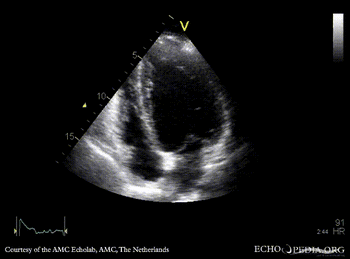

Endocarditis of aortic valve

A4CH: dilated left ventricle A5CH: vegetations on aortic valve, dilated left ventricle